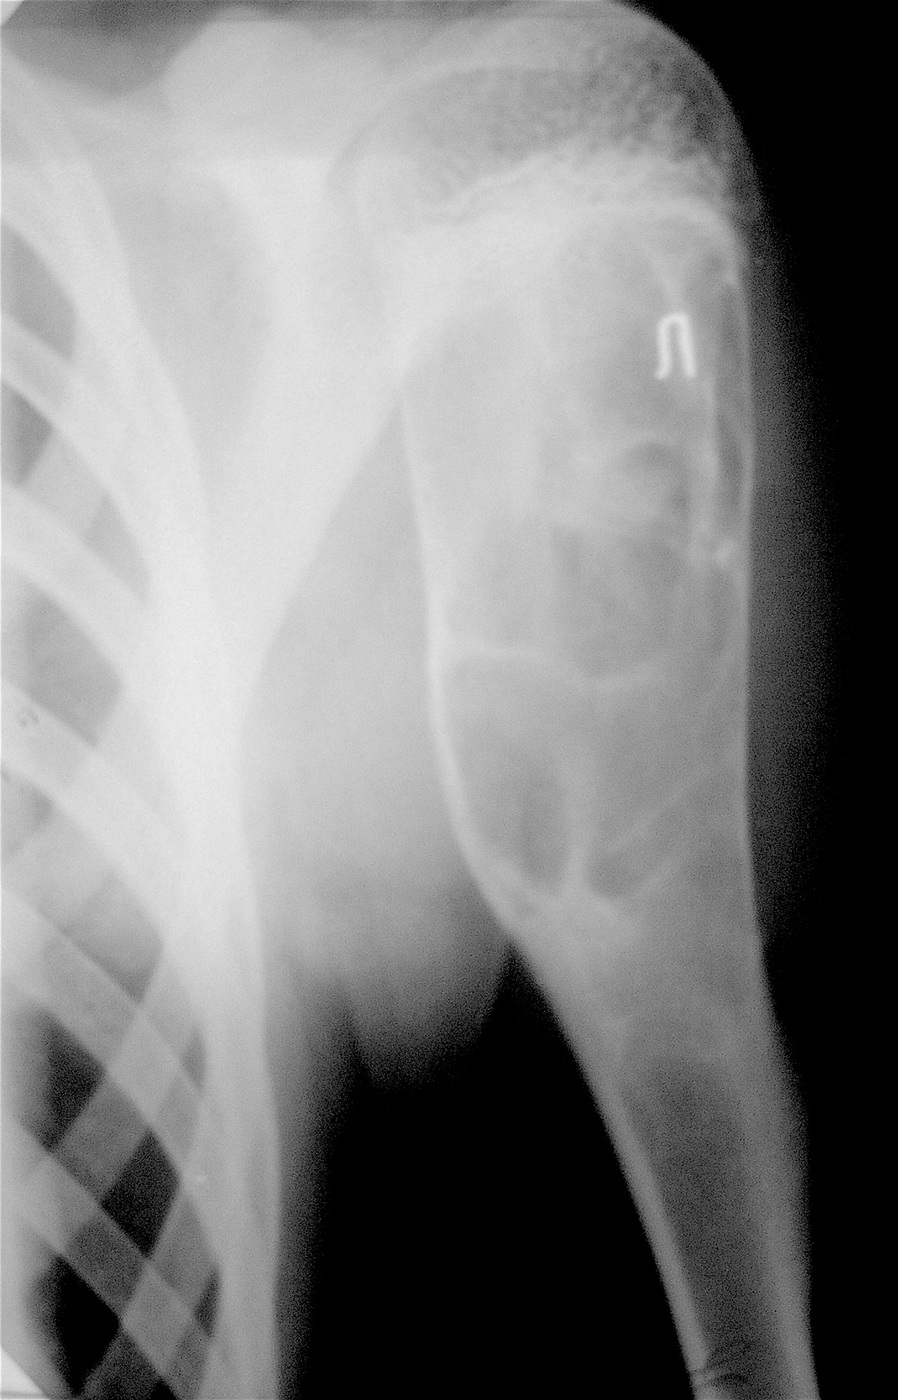

Аневризмальная киста проксимального метафиза левой плечевой кости.

Выполнена операция: экскохлеация кисты, аллопластика материалом «Лиопласт».